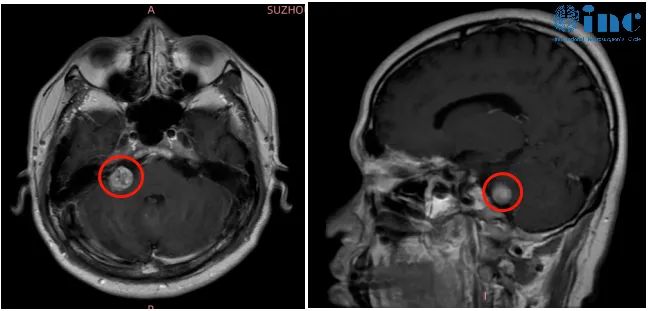

30余岁女性患者2019年始发耳部闷胀感,多次检查未见异常。2021年症状加剧,出现站立不稳、视力下降等表现,MRI确诊为3.5厘米听神经瘤压迫脑干。经过个体化手术入路结合神经电生理监测,实现肿瘤全切并保留面部功能。术后两年随访无复发迹象。